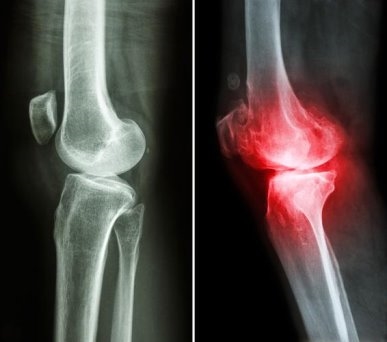

骨关节炎是一种以关节软骨磨损、破坏等为特征的慢性退行性疾病。当失去了软骨的缓冲,关节间直接摩擦,遇寒、受潮时就容易诱发炎症。而氨糖是合成软骨细胞的核心原料,也是构成软骨基质与关节液的基础成分。它不仅能修复受损软骨组织,还可补充关节滑液,降低摩擦,同时通过抑制关节腔内的炎症因子,有效延缓骨关节炎的发展进程[1]。

同时,维固力能够有效缓解关节不适这一点,得到了世界顶级医学期刊《柳叶刀》的证明。《柳叶刀》一项研究表明,治疗膝骨关节炎时,长期服用维固力可显著减轻关节疼痛程度约4倍[3],提升关节功能指数约2倍[4],延缓关节间隙变窄的程度约4倍[5],从根源改善关节结构,延缓关节磨损。